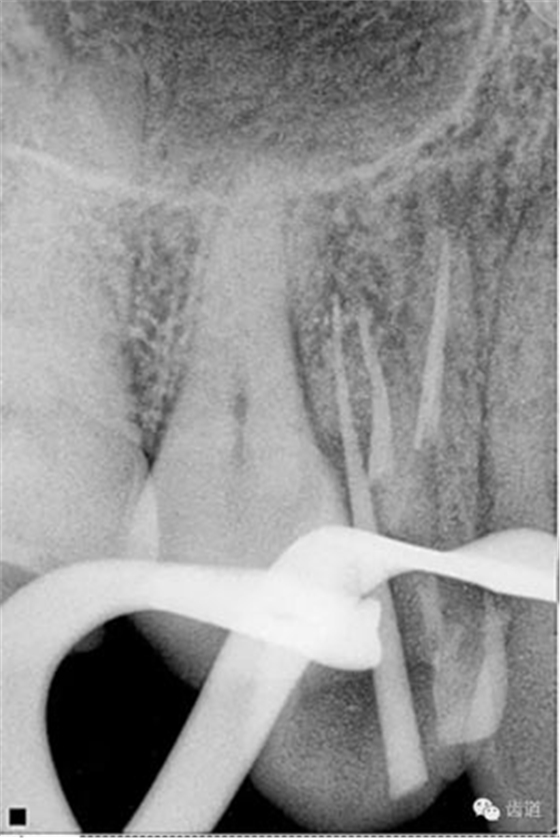

檢查顯示:近頰及腭根充填恰填,遠(yuǎn)頰根管內(nèi)有少許充填物影像。根尖明顯低密度影像。

處理:顯微根管治療。放置橡皮障,去除暫封,顯微鏡下超聲去除頰側(cè)根管上段部分牙本質(zhì),探及遠(yuǎn)中根管口,見(jiàn)有糊劑遮蓋。Pathfile根管疏通,MTwo根管預(yù)備至2506#,配合3%次氯酸鈉和17%EDTA超聲蕩洗,干燥根管,放置氫氧化鈣糊劑,zoe暫封。